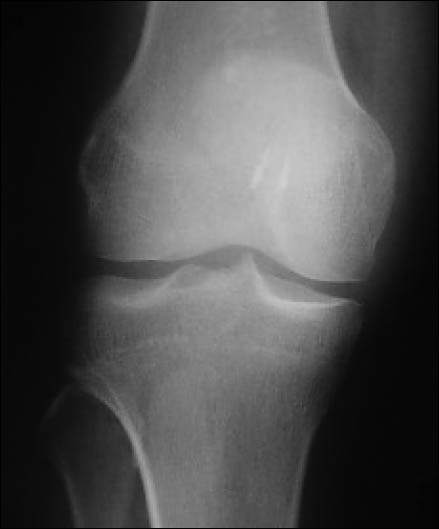

Rx con incidencias de frente y perfil de rodilla. (Fig. 1)

Figura 1: Rx perfil, rótula alta, hallazgo: encondroma de fémur distal.